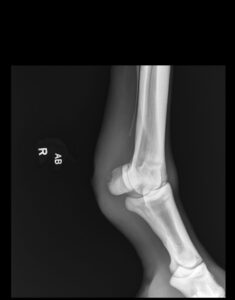

“Two days later, Ranger became suddenly lame again. Radiographs revealed septic sesamoiditis, a serious bone infection. With the same determination, our field service team performed a standing procedure to debride the infected bone as much as possible. Ranger remained on oral antibiotics for a few more weeks as we all hoped he would have the strength and determination to kick the infection,” Clough said.